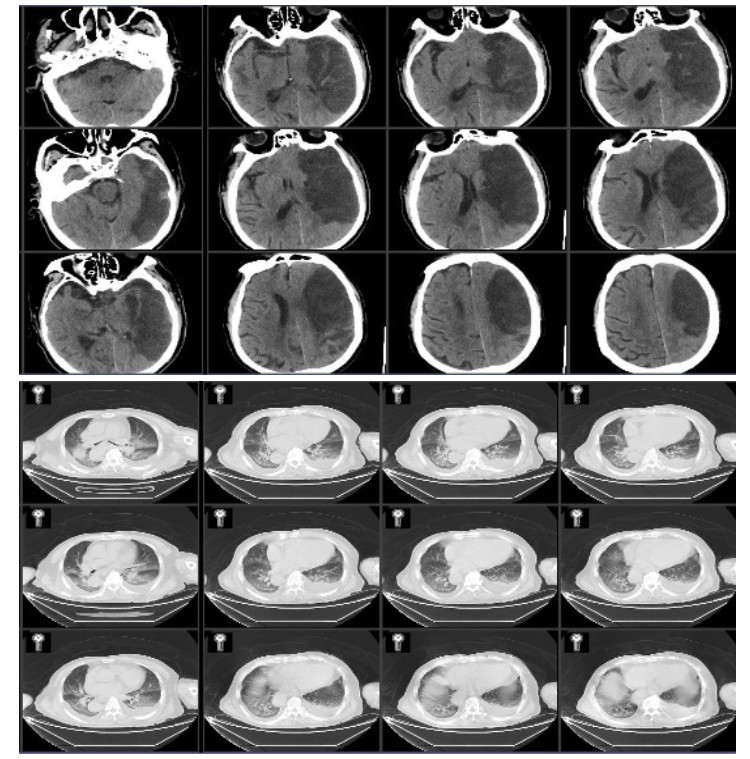

第8天复查肺部CT提示肺部感染(图 2),给予头孢他啶2.0 mg 2次/d抗感染治疗。患者第9天上午9时,患者突发心悸,气急,言语含糊。查体:体温37.3 ℃,脉搏100次/min,血压170/80 mmHg (1 mmHg=0.133 kPa),呼吸25~40次/min,指末氧饱和度SPO2 89%~95%,GCS 2-2-5分,双瞳等大等圆,光敏,双肺呼吸音减低,可闻及少量哮鸣音。血气分析:pH 7.344↓,PCO2 6.76 kPa↑,PO2 6.83 kPa↓,pro-BNP 513.3 pg/mL↑,PCT 0.09 ng/mL;血常规:WBC 9.46×109/L,NEUT% 78.5%↑;血电解质、心肌标志物、心肌酶谱、心超和心动图未见明显异常。经呼吸科和心内科会诊对症治疗后呼吸平稳,血氧饱和度维持95%以上。

| 图 2 患者第8天肺部CT |

病例2,男性,80岁,因“突发右侧肢体无力1周,加重伴意识障碍1 d”由外院转入我院。外院头颅CT示左侧额颞叶片状低密度灶,诊断大面积脑梗死。头颅CTA示左侧颈内动脉及大脑中动脉部分闭塞,急诊溶栓治疗无效。既往有高血压病史20年,无冠心病房颤病史。入院查体:生命体征平稳,体温37.8 ℃,GCS 2-5-1,双瞳等大等圆,光敏,左侧肢体有不自主活动,右侧肢体无活动,右侧巴氏征阳性。入院诊断为左额颞大面脑梗,肺部感染,高血压病。入院后头肺CT见图 3。

| 图 3 入院患者头颅和肺CT |